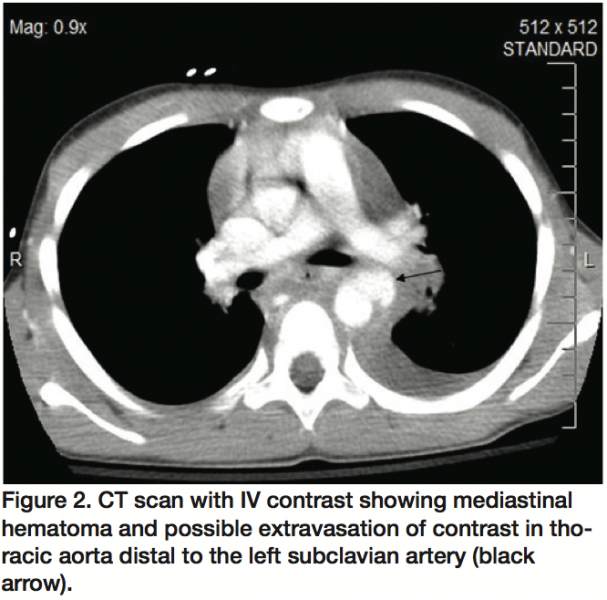

A 10-year-old boy was involved in a pedestrian versus motor vehicle accident at unknown speed. The patient sustained injuries to the chest, head, and lower extremities. The patient was initially seen at an outside hospital and after stabilization, he was transferred to our institution. The primary survey noted a 14 on the Glasgow Coma Scale; he was hemodynamically stable with a pulse rate of 120/min and blood pressure of 150/75. Physical examination was remarkable for anisocoria (right pupil 7 mm mildly reactive, left pupil 3 mm reactive); tenderness to left chest, mid-sternum, and epigastrium with a deformity of the right lower extremity. Femoral and distal pulses were present and symmetrical. Review of outside films, including a computed tomography (CT) of the head, did not reveal any evidence of intracranial bleed. Initial serum hemoglobin level was 9.5 g/dl; white blood cell count was 20.4; chest x-ray revealed a widened mediastinum, left apical pleural effusion, and deviation of trachea to right (Figure 1). Focused assessment with sonography for trauma (FAST) exam did not reveal any evidence of intra-abdominal bleed. An x-ray of right lower extremity revealed comminuted fracture of proximal tibial and fibular shaft. A chest CT revealed a mediastinal hematoma, with possible extravasation of contrast in the descending thoracic aorta (Figure 2).